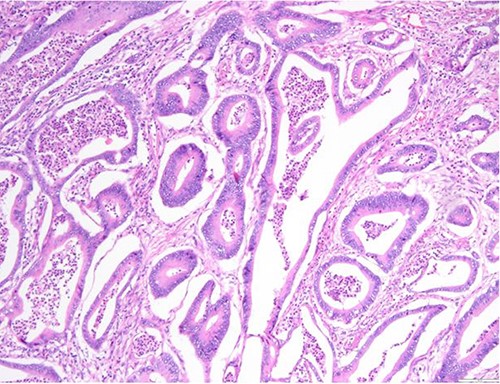

Surgical specimen: hysterectomy; microscopy, HE; endometrium and myometrium infiltrated by well-formed neoplastic glandular structures composed of cells with ‘pencillated’ and atypical nuclei, with nucleoli, apoptosis and mitotic figures, consistent with an intestinal origin (metastatic colorectal adenocarcinoma).

Surgical specimen: hysterectomy; microscopy, HE; endometrium and myometrium infiltrated by metastatic colorectal adenocarcinoma.